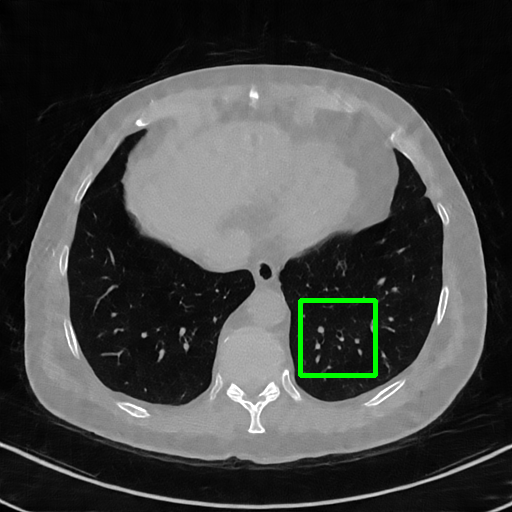

Generalizablity on COVID-19 dataset. Finally, we use slices of another patient in the COVID-19 dataset to test the generalizability of trained models, and quantitative performances are compared in Table 4. ImgTrans and DuDoTrans have achieved a larger improvement about 4-5 dB over CNN-based methods, which shows that the long-range dependency modeling ability helps capture the intrinsic global property of general CT images. Further, our DuDoTrans exceeds ImgTrans about 0.4 dB in all cases, even larger than the original NIH-AAPM dataset. The improvement ensures that DuDoTrans generalizes well to out-of-distribution CT images. Besides, we also show the visualization images in Fig. 5 when = 96. Coinciding with the quantitative comparison, our DuDoTrans show better reconstruction on both global patterns and local details.

Ground Truth

FBP

FBPConvNet

DuDoNet

ImgTrans

DuDoTrans